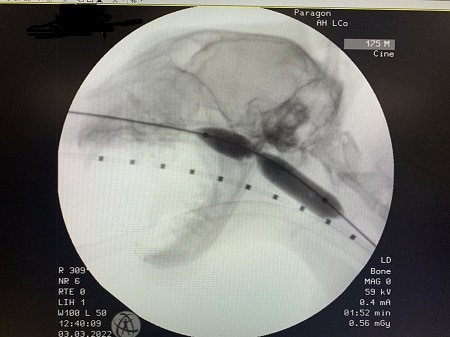

Internal medicine specialist and head of service Andrea Holmes; internal medicine specialist Lizzy Conway and internal medicine intern Simona Borgonovi performed a balloon dilation under fluoroscopy and endoscopy guidance to cure the issue.

Simona said: “The procedure involved the use of an inflatable balloon which was progressively dilated to breakdown the stenosis and help Rupert to be able to breathe silently again.